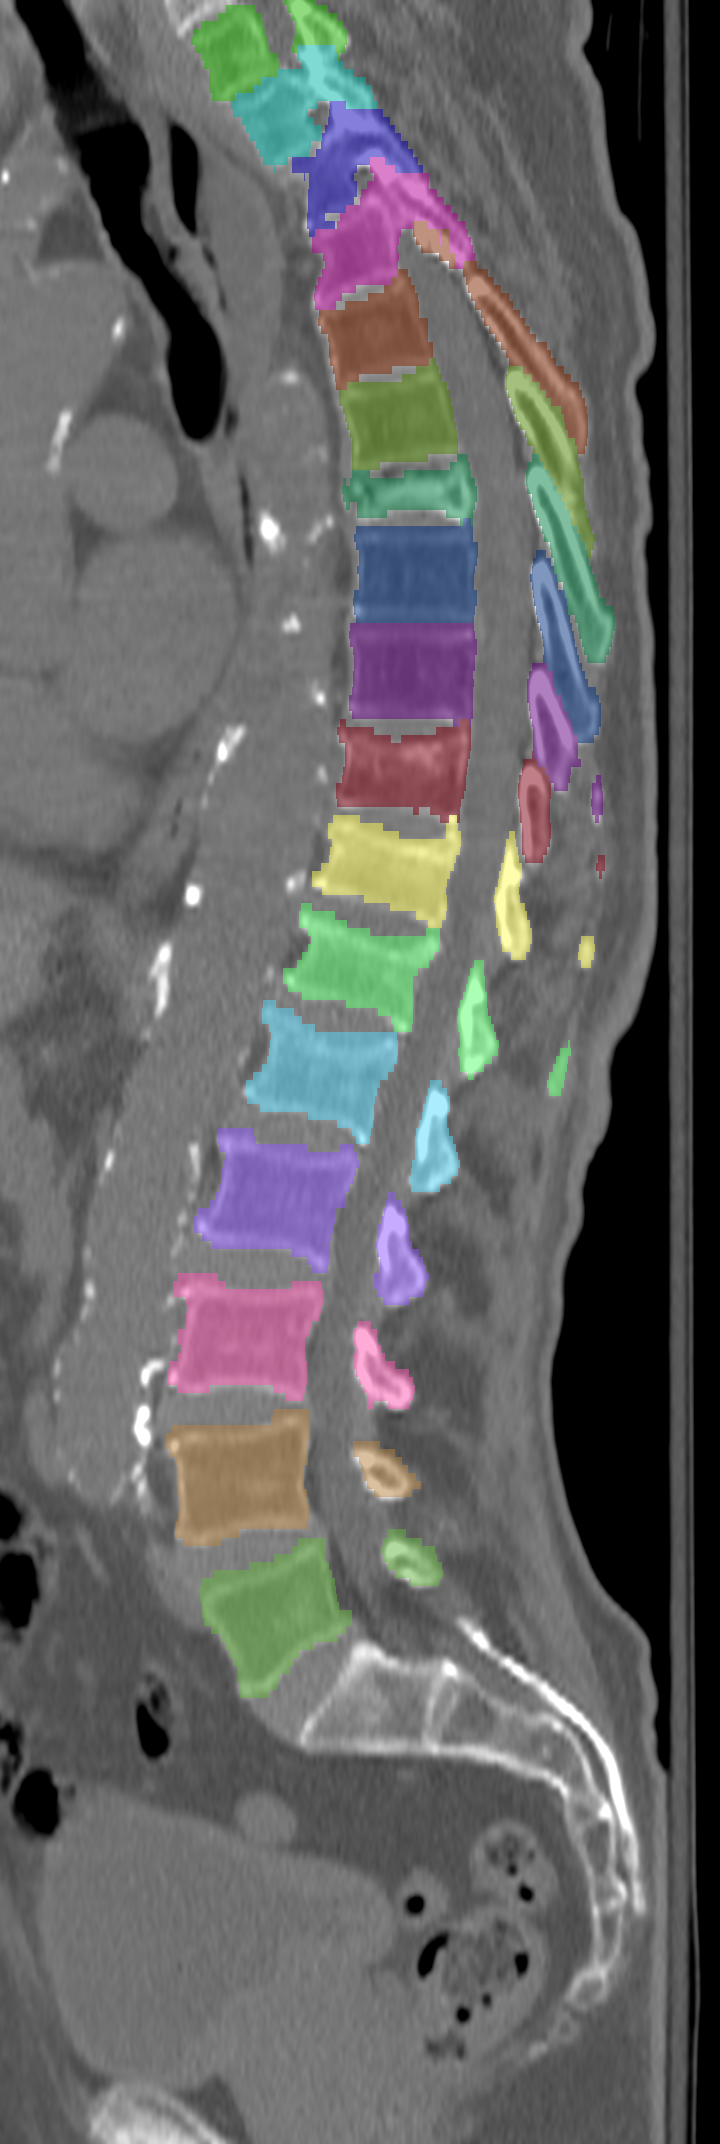

Normalized CT images and reference segmentations of thoracic and lumbar vertebrae from the CSI 2014 workshop

This is the dataset of the vertebra segmentation challenge of the CSI 2014 workshop that was held in conjunction with MICCAI 2014.

- 16-20: Test set, scans of 5 patients with vertebral compression fractures

- Vertebrae have been anatomically labeled (8 = T1, 9 = T2, ..., 24 = L5)

- Because not always all visible vertebrae were segmented in the original data, only segmentations of the thoracic and lumbar vertebrae have been retained

The resolution and segmentation quality of the diseased cases (16-20) is quite low.